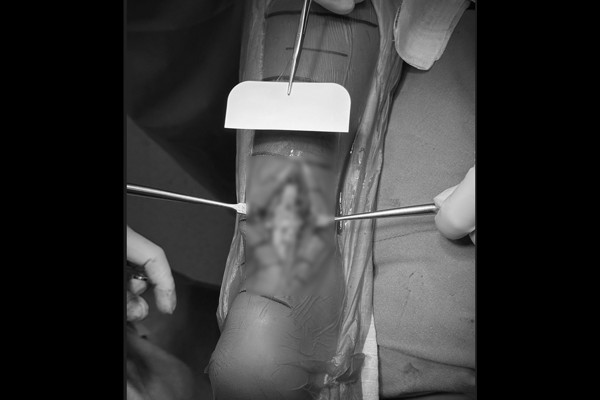

견고하게 다중봉합된 아킬레스건이 확인됩니다.